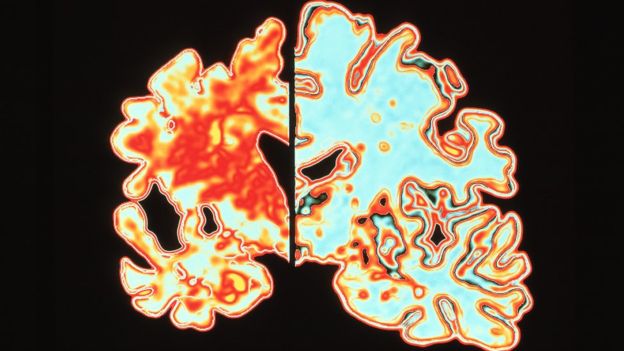

Os sintomas são um reflexo da morte de células do cérebro. A doença é neurodegenerativa, o que significa que uma pessoa com Alzheimer passa a ter cada vez menos células e conexões nervosas.